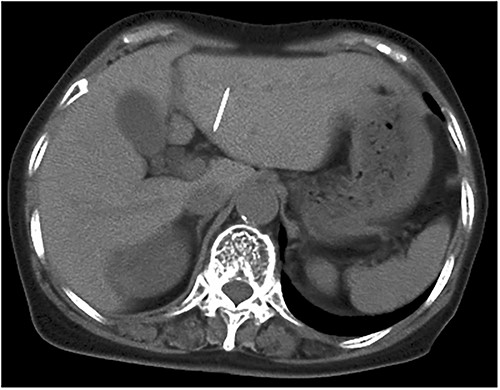

An 81-year-old woman presented to our hospital with an abnormal shadow on her abdominal X-ray performed during a gastrointestinal checkup. She had no subjective symptoms. She had no comorbidities other than hypertension and no history of laparotomy. Her vital signs were normal. No foreign body was palpable on the abdominal wall, chest wall, or back. No mental abnormality or cognitive impairment was noted. A plain abdominal radiograph showed a needle-like shadow at the second lumbar vertebra level (Fig. 1). Abdominal computed tomography (CT) displayed a needle-like shadow obliquely directed from the inferior surface of the liver to the lateral segment. No intrahepatic or intraperitoneal abscess was observed (Fig. 2). Upper gastrointestinal endoscopy revealed no stomach or duodenal ulcer scarring. Detailed history revealed no history of trauma or acupuncture treatment and no memory of accidental ingestion of needles. No subjective symptoms such as sore throat or epigastric pain were reported. Based on these findings, a sewing needle was accidentally swallowed without awareness, perforating at the pylorus of the stomach or duodenal bulb and straying into the liver. The patient had no symptoms at the time of the visit, and we told her that she could be followed up. However, the patient strongly desired needle removal; therefore, we decided to perform a laparoscopic resection. Laparoscopic observation revealed fibrous adhesion between the lesser curvature of the gastric pylorus and the inferior surface of the outer hepatic segment. When the adhesion was detached, the foreign body tip was observed on the subhepatic surface. It was grasped with forceps, extracted, and removed from the abdominal cavity (Fig. 3). A sewing needle of ~3-cm length was removed (Fig. 4). The patient had a good postoperative course and was discharged from the hospital on postoperative Day 4 without any complications.

Abdominal CT scan displaying needle-like shadows obliquely lying in the left lateral segment of the liver.